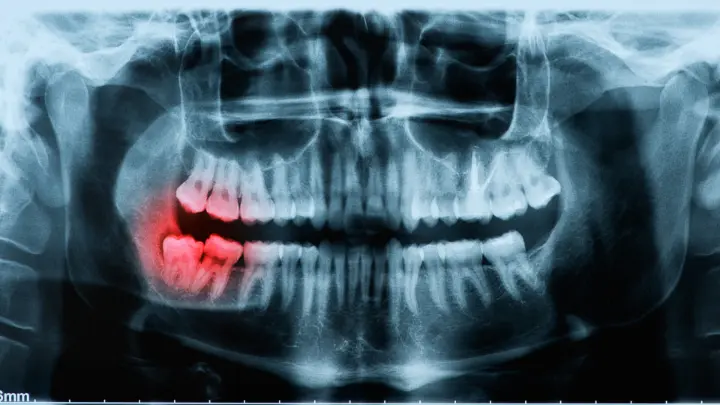

Masalah muncul karena akar gigi bungsu rahang bawah sering kali berada sangat dekat dengan jalur saraf ini. Ketika gigi bungsu impaksi harus diangkat melalui tindakan bedah, terdapat kemungkinan saraf mengalami tekanan, iritasi, atau bahkan cedera.

Dalam artikel tersebut, peneliti melaporkan sebuah kasus pencabutan gigi molar ketiga rahang bawah kiri. Untuk memudahkan proses pencabutan, dokter melakukan teknik pemisahan gigi (tooth sectioning)—teknik yang umum digunakan dalam operasi gigi bungsu.

Namun selama prosedur berlangsung, sebagian akar gigi berpindah ke ruang submandibular. Komplikasi ini kemudian menyebabkan infeksi dan memerlukan tindakan operasi lanjutan oleh dokter bedah mulut dan maksilofasial.